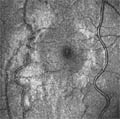

α) το HRT II, ένα ομοεστιακό σύστημα σάρωσης με laser, που παρέχει τη δυνατότητα της τρισδιάστατης απεικόνισης του αμφιβληστροειδή και συντελεί στην αξιολόγηση της ωχράς κηλίδας και στην εκτίμηση της τοπογραφίας του οπτικού δίσκου. Με την προσθήκη ενός αντικειμενικού φακού, το ίδιο σύστημα χρησιμοποιείται και για την απεικόνιση του κερατοειδή in vivo.

Απεικόνιση αμφιβληστροειδή | Απεικόνιση κερατοειδή |

![]() | ![]() |